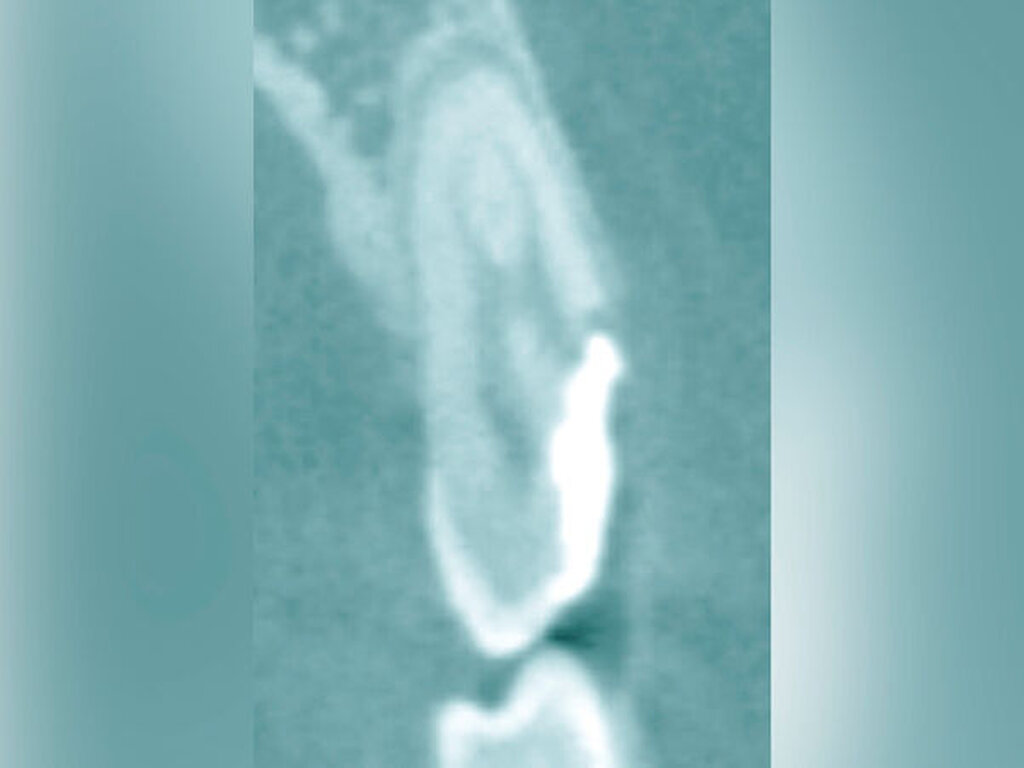

Bei der chirurgischen Extrusion (Synonym: intra-alveoläre Transplantation) wird der betroffene Zahn oder die betroffene Wurzel chirurgisch weiter koronal positioniert, um die Anfertigung einer adäquaten Restauration zu ermöglichen. Ihr biologisches Prinzip ist eingehend beschrieben worden mit guten Erfolgen im Tiermodell [Oikarinen et al., 1996] und in der klinischen Anwendung [Caliskan et al., 1999; Das und Muthu, 1999; Krug et al., 2018]. Die Technik wird bisher kaum in der zahnärztlichen Praxis angewendet, vermutlich aufgrund der begrenzten Vorhersagbarkeit, einen schwer kompromittierten Zahn oder eine Zahnwurzel erhalten zu können, wenn auf konventionelle Art und Weise extrahiert wird. Zum einen besteht das Risiko, durch die Extraktion eine Zahnfraktur zu verursachen, die den Zahnverlust zur Folge hat. Zum anderen führt die Anwendung von Luxatoren, Elevatoren oder Periotomen zu einer Aufdehnung der Alveole sowie zu Schäden am parodontalen Gewebe und gegebenenfalls an der Zahnwurzel selbst. Die Herausforderungen bei einer Zahnmobilisation für eine chirurgische Extrusion bestehen darin, weiteren Schaden an den Strukturen von Zahnhartsubstanz, Knochen und parodontalem Ligament zu vermeiden. Gelingt dies, können deren Hauptrisiken wie Zahnfraktur und progressive Wurzelresorption minimiert werden [Elkhadem et al., 2014].

Zur chirurgischen Extrusion werden meist Extraktionszangen verwendet. Die Zahnwurzel wird dabei idealerweise mit einer diamantierten Zange gefasst und durch Rotation vorsichtig entfernt. Insbesondere bei Zähnen mit runden Wurzeln ist diese Technik auch weitgehend schonend für das parodontale Ligament. Der forcierte Einsatz von Hebeln oder Luxationsbewegungen ist zu vermeiden, da diese zu parodontalen Schäden auf der Wurzeloberfläche führen können und somit die parodontale Heilung nach Replantation gefährden.

Eine weitere Möglichkeit, tief zerstörte Zähne möglichst schonend chirurgisch zu extrudieren, basiert auf axialen Zugsystemen (Abbildungen 2 bis 4). Diese erscheinen vorteilhaft bei sehr schwierigen Fällen, zum Beispiel bei Zähnen mit fehlendem Ansatzpunkt für die Zange sowie bei langen oder sehr ovalen Wurzeln. Axiale Zugsysteme ermöglichen die Übertragung von Zugkräften auf die Zahnwurzel, ohne die Alveole unnötig zu dehnen. Dazu wird eine spezielle Schraube in den Wurzelkanal eingebracht und das Gewinde der Schraube für eine ausreichende Friktion fingerfest eingedreht. An diese Schraube wird ein gerätespezifisches Zugsystem angelegt. Durch rein axial wirkende Zugkräfte werden traumatische Effekte auf Knochen und Wurzeloberfläche während der Zahnmobilisation minimiert. Gegebenenfalls können feine Luxatoren vorsichtig unterstützend eingesetzt werden. Im Tiermodell wurde an extrahierten und wieder replantierten Zähnen mit ovalem Querschnitt gezeigt, dass der Verlust von Zementoblasten auf der Wurzeloberfläche geringer ist, wenn ein axiales Zugsystem anstatt einer Extraktionszange verwendet wird.

Die wesentliche technische Komplikation stellt das unverhältnismäßige Erweitern des Wurzelkanals für die Retention des Zughilfsmittels – zum Beispiel der Benex-Schraube – dar. Der Behandler sollte hier unter besonderer Vorsicht den bereits instrumentierten und präparierten (vorgegebenen) Wurzelkanal als Bohr- und Zugpfad für die Extrusion nutzen. Auf die Schonung der gesunden Zahnhartsubstanz muss geachtet werden. Die Bohrachse für die Ausrichtung der Zugschraube muss mit dem koronal gelegenen Hauptpfad des Wurzelkanals übereinstimmen. Zudem ist für das Erzielen einer ausreichenden Retention der Schraube ein gewisses Maß an Feingefühl und Taktilität vom Behandler erforderlich. Eine neue Schraube erfüllt die Vorbedingung eines schneidfreudigen Gewindes und damit eines guten Halts im Zahn am besten.